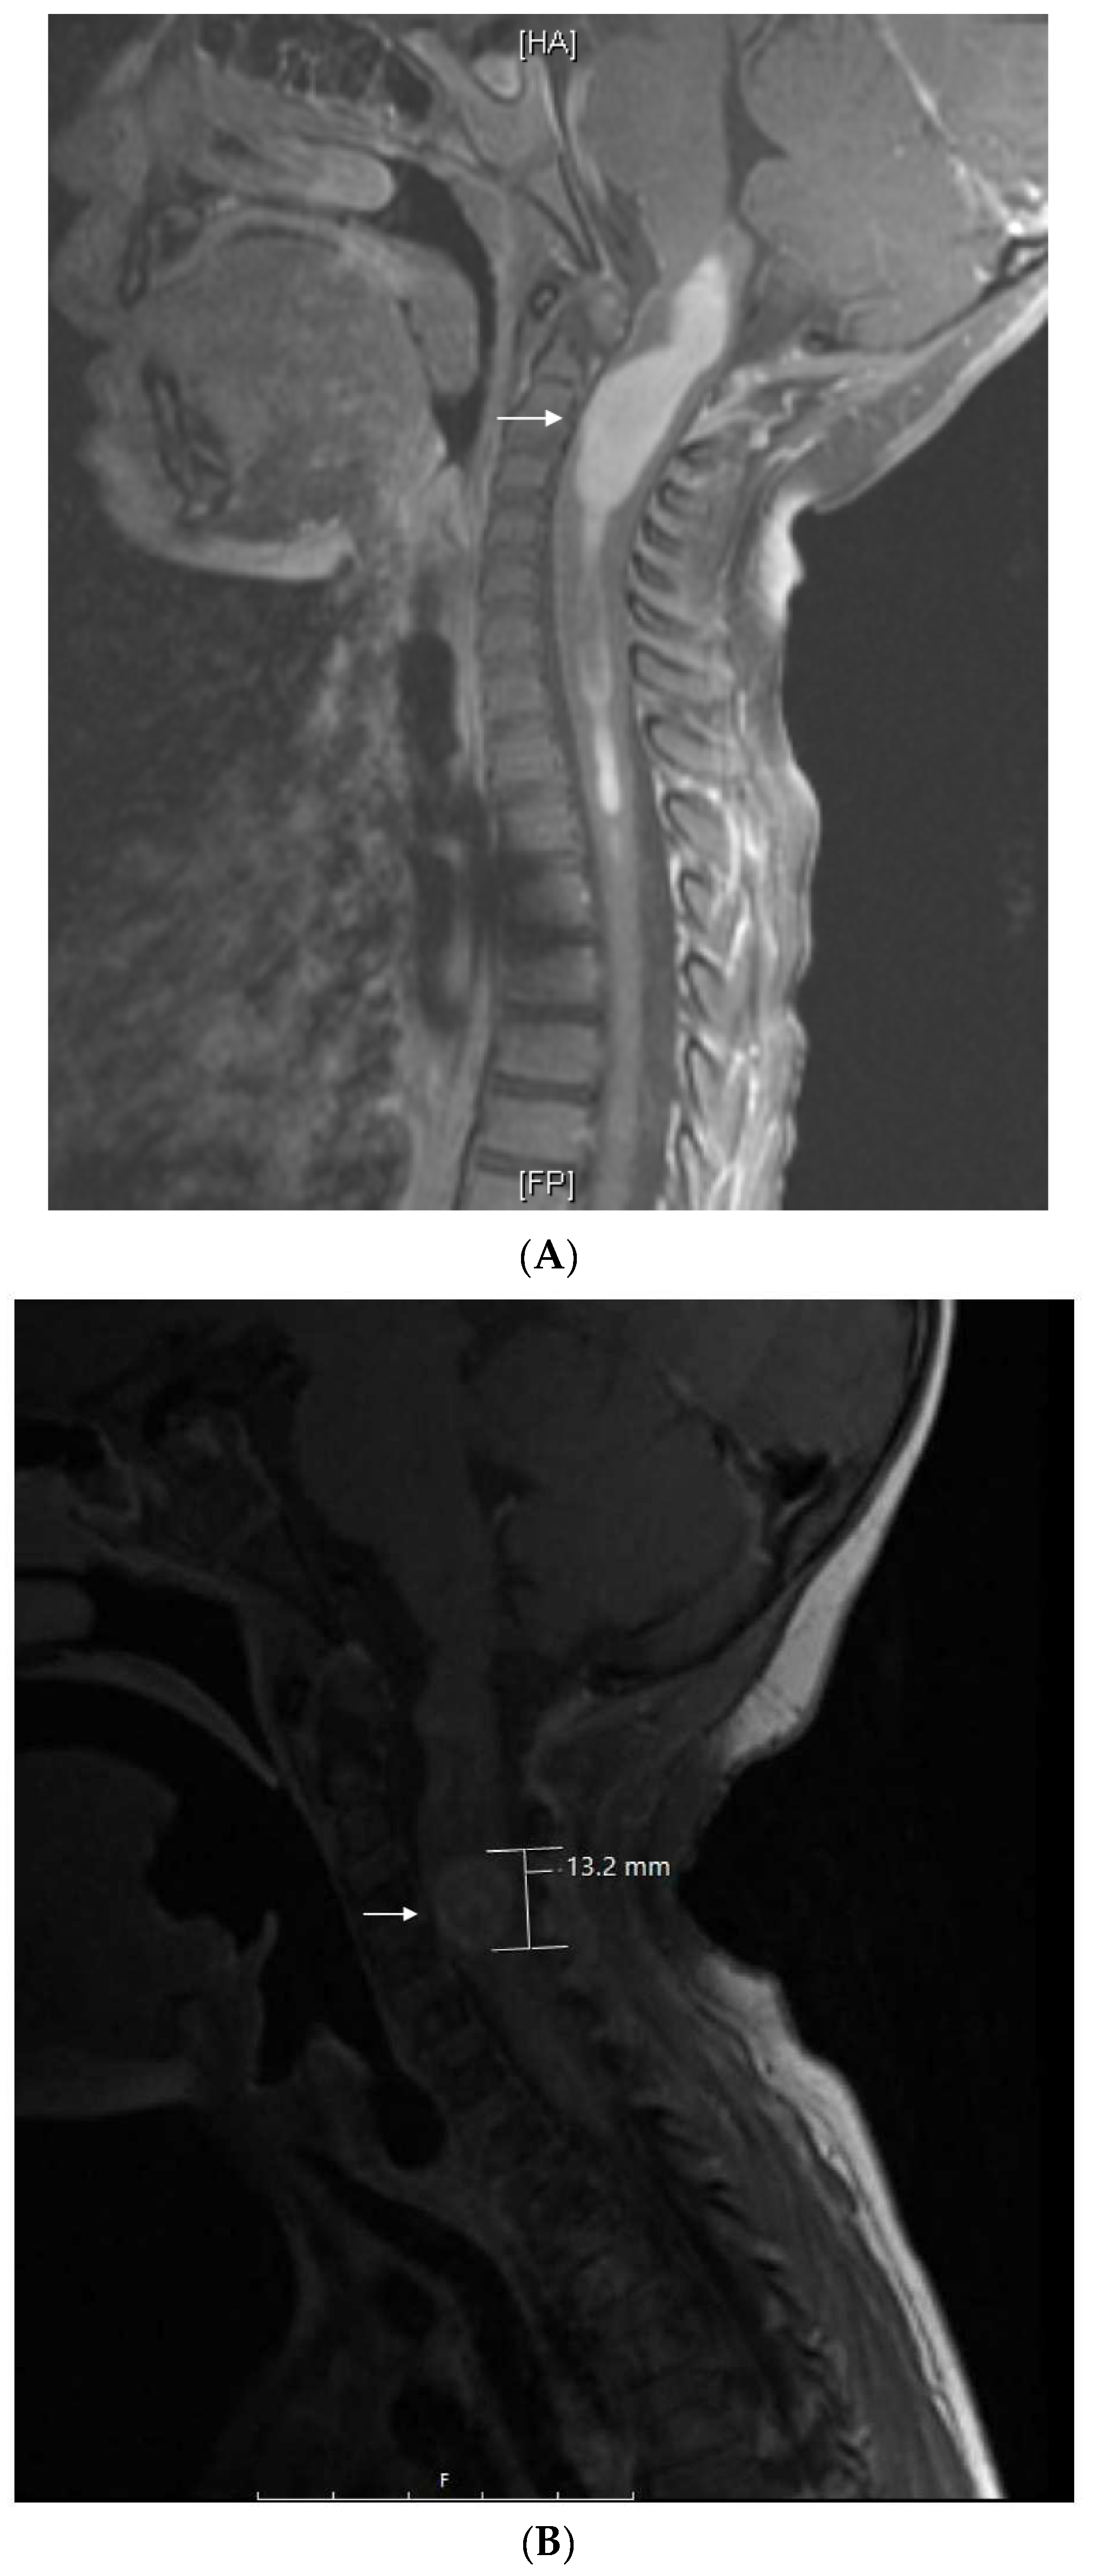

This patient is a Hispanic girl found to have a large cervicomedullary tumor with a cervico-thoracic central syrinx with tumor seeding when she presented with right shoulder drop and right upper-extremity weakness at 3 years of age (Figure 4A). She had resection of the cervicomedullary portion of the tumor. Evaluation revealed a type 2 neurocytoma of the spine.

Figure 4.

Patient 6: (A) MRI shows a 4.5 cm homogeneously enhancing expansile intramedullary tumor involving the medulla and upper cervical cord down to the level of C3–C4 (arrow) with an elongated syrinx extending inferiorly to the T3–T4 level; (B) the tumor was removed and treated with radiation but came back, for which it was treated with nine cycles of topotecan–ifosfamide–carboplatin with no significant change in tumor size (arrow) but significant toxicity, for which treatment was changed to metronomic chemotherapy; (C) after 3 months on metronomic chemotherapy, the patient recovered from toxicity and the tumor was slightly decreased; (D) the tumor was stable at the end of 4 years of metronomic chemotherapy.

She subsequently received intensity-modulated radiotherapy to the tumor bed and residual cervico-thoracic tumor. Following radiation, a residual 11 mm expansile cervicomedullary nodule, centered at the C3–C4 level, was documented. Five months later, she developed progressive disease with increased size of the cervicomedullary nodule to 15 mm and development of a new second focus of enhancement on the ventral aspect of the spinal cord at C2. She was treated with topotecan, ifosfamide and carboplatin (TIP). She had significant hematologic toxicity and infectious complications during this treatment and no change in tumor size after nine cycles (Figure 4B), for which she was changed to metronomic chemotherapy with 21 days of temozolomide (60 mg/m2 day) aleternating with 21 days of CTX (50 mg/m2), VA (15 mg/kg), celecoxib (250 mg/m2/day) and bevacizumab (5 mg/kg IV every 3 weeks). Tumor response was noted 3 months after treatment with decreased tumor size to 9–10 mm (Figure 4C). Tumor size remained stable on subsequent studies, and temozolomide and CTX were stopped at 18 months, celecoxib and VA were stopped at 36 months, and bevacizumab was stopped at 48 months (Figure 4D). Metronomic chemotherapy was restarted after tumor progression was documented 10 months later (Table 1). She developed stable disease and treatment was stopped 15 months later. She remains with stable disease 4 years off therapy.